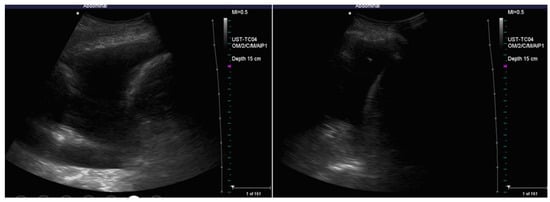

4. Ultrasound-Assisted Procedure

- anechoic (without echoic images);

- complex non-septated (echogenic material is detected inside the effusion);

- complex septated (floating fibrin strands or septs are found inside the effusions);

- homogenously echogenic.